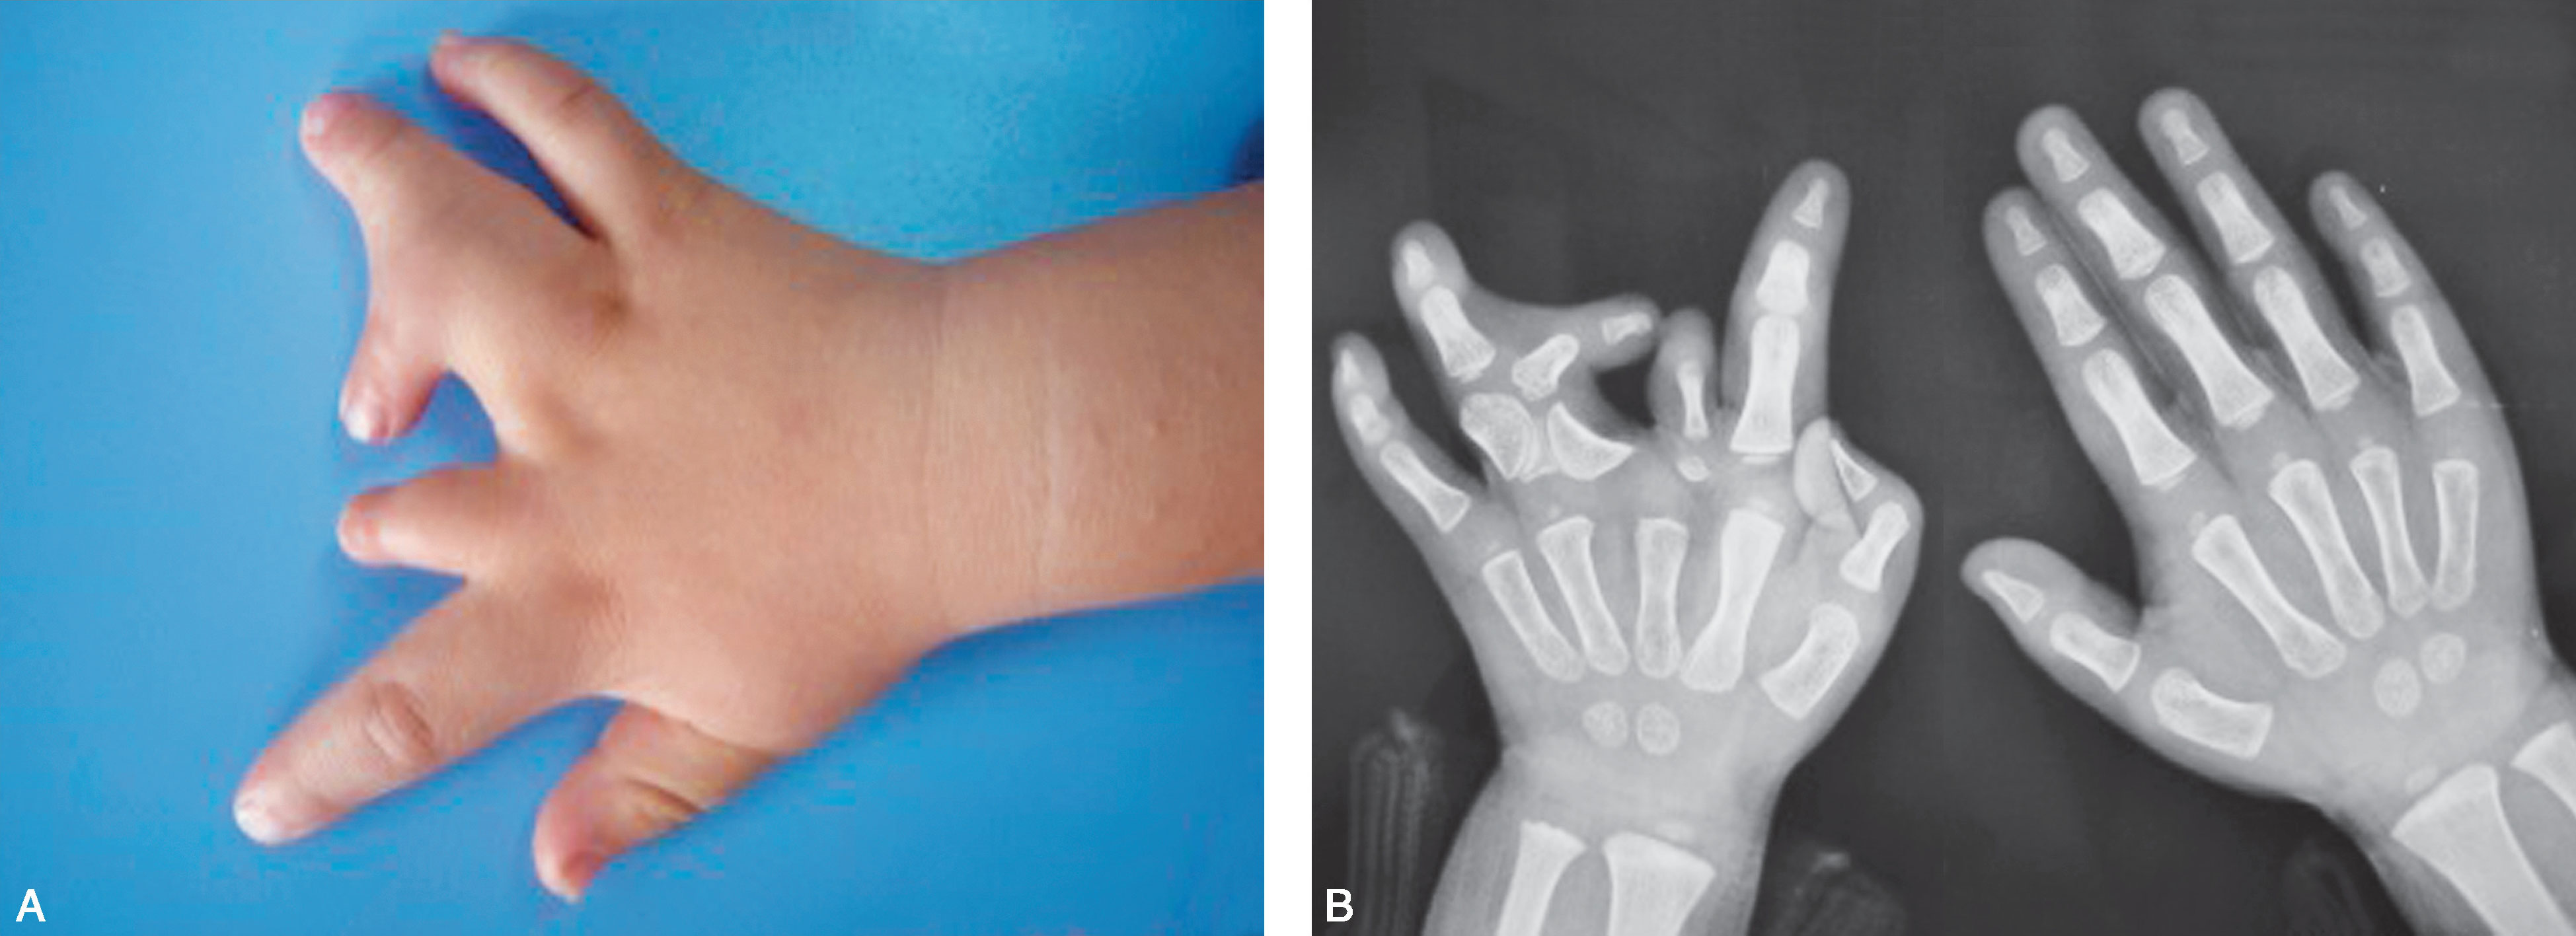

图1-2-2 先天性缺指病例

A.左侧先天性手示、中、环指掌指关节水平缺如,小指远侧指间关节桡侧“肉赘样”赘指;B.X 线片显示示、中、环指掌指关节以远骨关节结构未发育